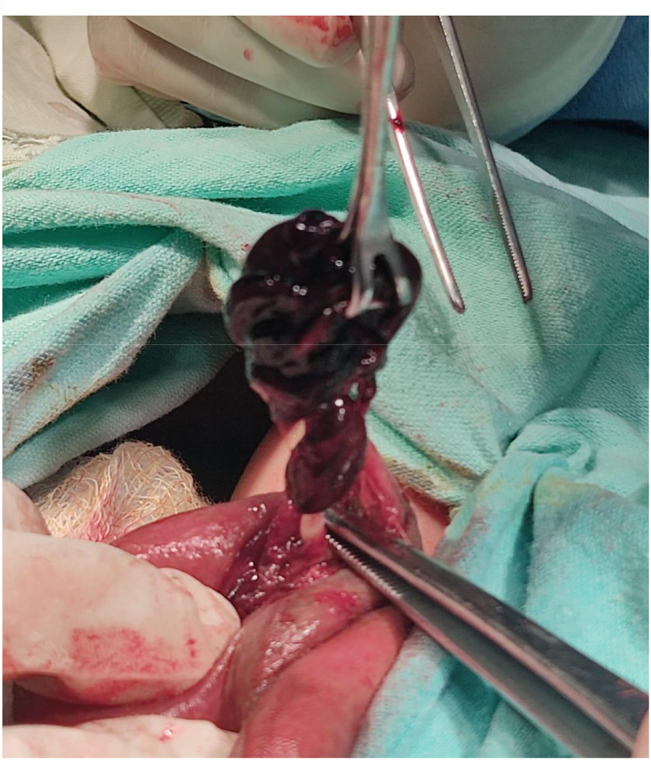

Case presentation: We present here the case of a two-day old neonate with in-born right scrotal swelling admitted at Children's hospital. The patient was born at term via cesarean section at a private hospital. Upon arrival in the emergency department, he was well hydrated, pink at room temperature with good perfusion. Upon examination, the right testis was found to be enlarged, tense, non-tender visibly reddish with overlying skin excoriation. Trans-illumination was negative in right but positive in the contralateral testis. Both hernial orifices were normal. Doppler ultrasound of the inguinoscrotal area found the right testis to be enlarged (15.6*9.4 mm) and showed heterogeneous hypoechoic texture with prominent rete testis and no flow on color doppler analysis. An urgent scrotal exploration was undertaken. Intra-operatively there was frank necrotic right testis with intravaginal torsion of the testis and minimal hydrocele. A right orchidectomy and contralateral orchidopexy were performed.